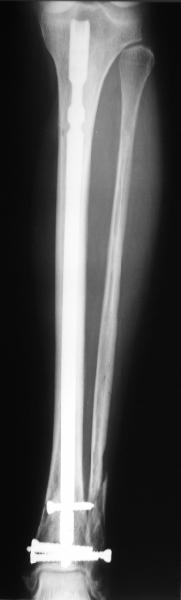

At least both the ankle mortise and tibial alignment look acceptable, don't they?

I am just trying to illustrate that prevention of 1)tibial valgus and 2)loss of reduction can be provided without fibular plating. Small changes of conventional nailing techniques allow to maintain reduction of the tibia reliably without adjunctive fibular stabilization.